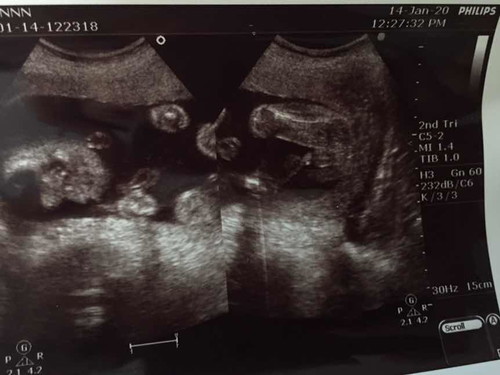

รูปอัลตร้าซาว

หมอบอกได้ลูกชายคะ แม่ๆท่านไหนได้ลูกเพศอะไรกันบ้างคะ

ลูกชายค่ะ. จุ๊ดจู๋ชัดมากค่ะ

ผู้ชายคร้า ชัดแจ๋วเลย 👶🏻❤️

ลูกชาย ชัดแจ๋วค่า 😊😊😊😊